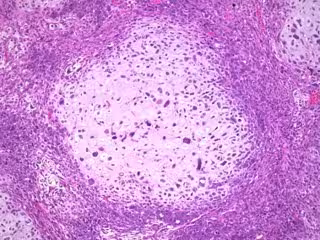

Sufrir un cáncer de mama predispone a desarrollar un cáncer ginecológico, según un estudio - WEBPATHOLOGY. VISUAL SURVEY OF SURGICAL PATHOLOGY